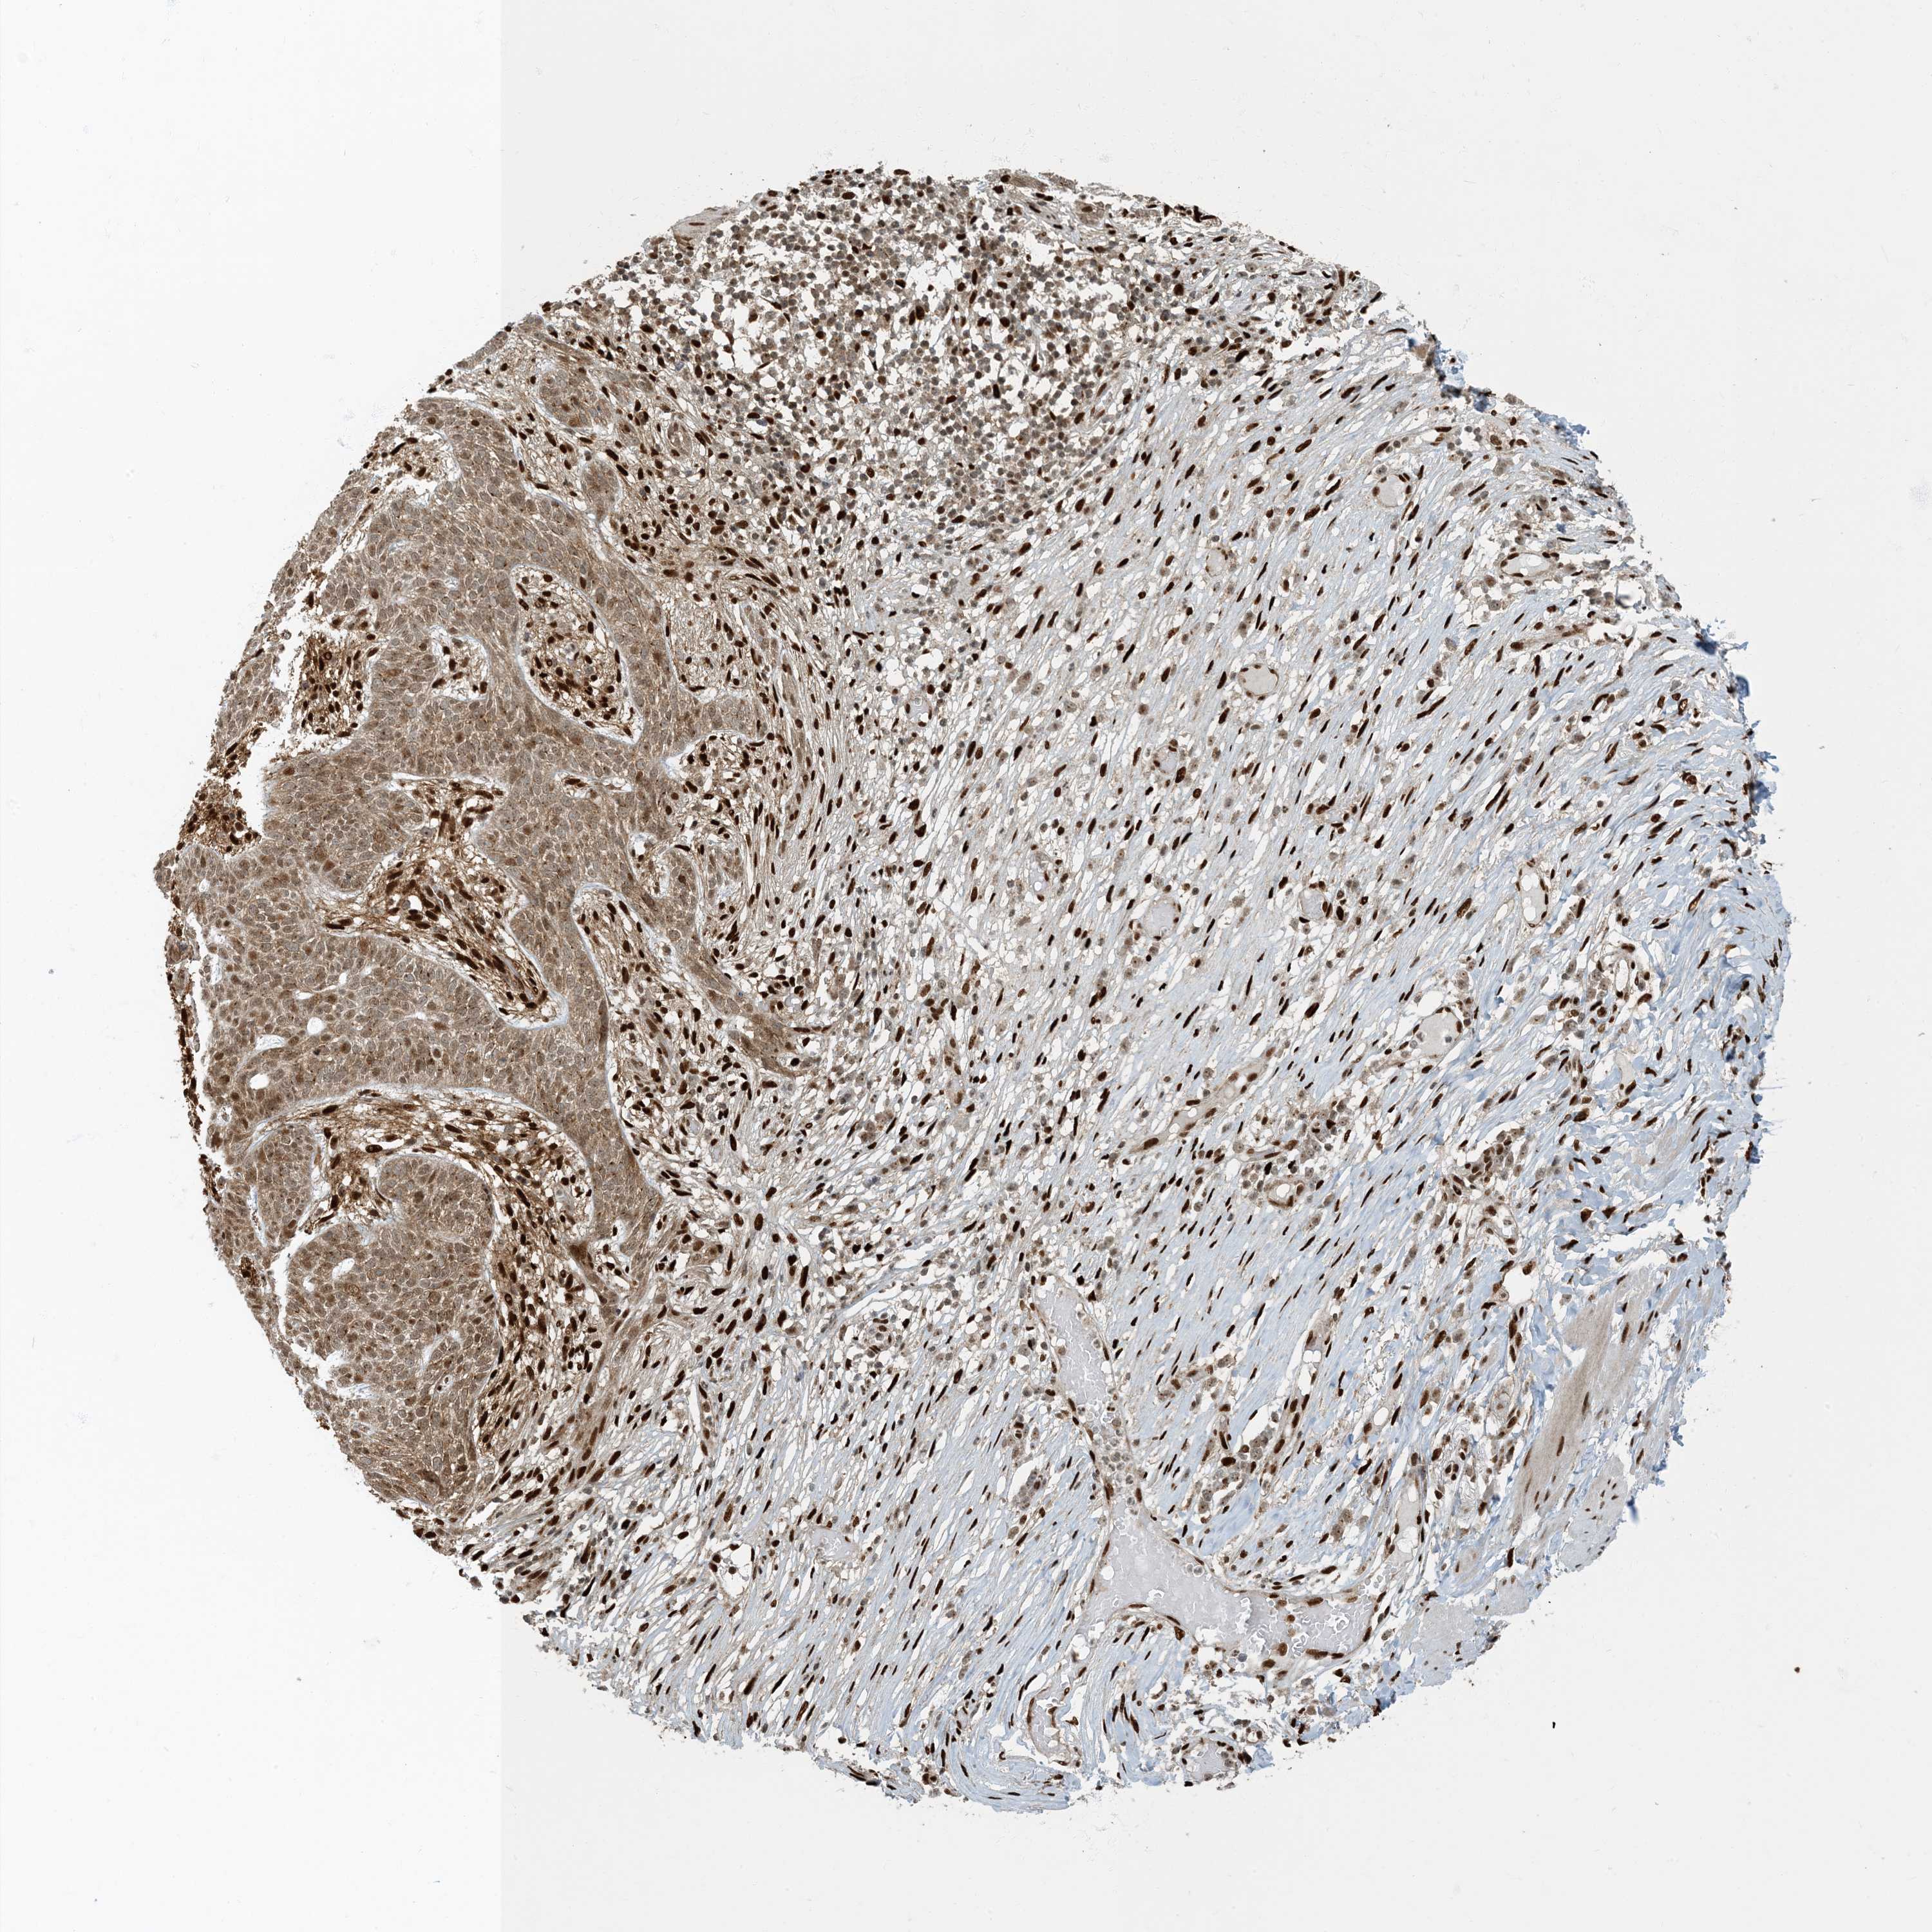

SKIN CANCER - Protein expressioni

A mouse-over function shows sample information and annotation data. Click on an image to view it in a full screen mode. Samples can be filtered based on level of antibody staining by selecting one or several of the following categories: high, medium, low and not detected. The assay and annotation is described here.

Each image is clickable and will lead to virtual microscopy that enables deeper exploration of all samples and also displays staining intensity scores, fraction scores and subcellular localization as well as patient and tissue information for each sample.

Antibody CAB036003

Staining

Medium

Intensity

Moderate

Quantity

75%-25%

Location

Cytoplasmic/membranous,nuclear

Squamous cell carcinoma, NOS

Squamous cell carcinoma, metastatic, NOS